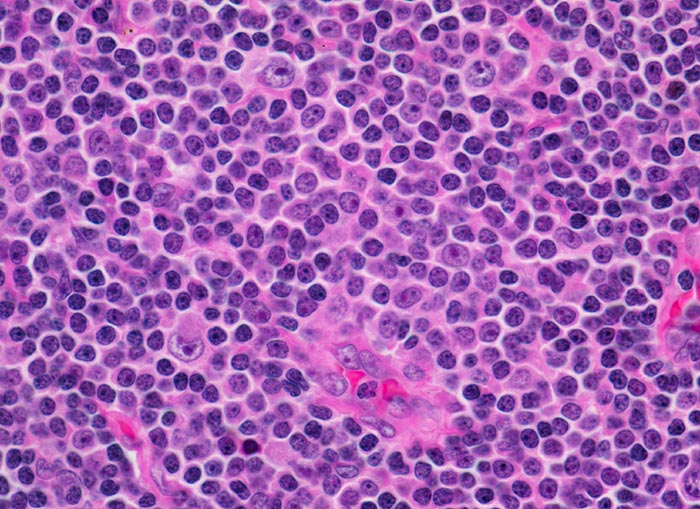

PathoPic – image database / PathoPic ID 3929 - chronische lymphozytische Leukämie vom B-Zell Typ

chronische lymphozytische Leukämie vom B-Zell Typ

Lymphknoten, inguinal

Ausschnitt aus einem Proliferationszentrum (Pseudofollikel) mit drei Zellpopulationen:

Kleine Lymphozyten mit wenig Zytoplasma und verklumptem dichtem Chromatin.

Etwas grössere Prolymphozyten mit feiner verteiltem Chromatin und kleinen Nukleolen.

Grosse Paraimmunoblasten mit runden bis ovalen Kernen, fein verteiltem Chromatin und einem zentralen Nukleolus.

Asymptomatische Patientin mit generalisierter Lymphknotenvergrösserung. Zufallsbefund.

630